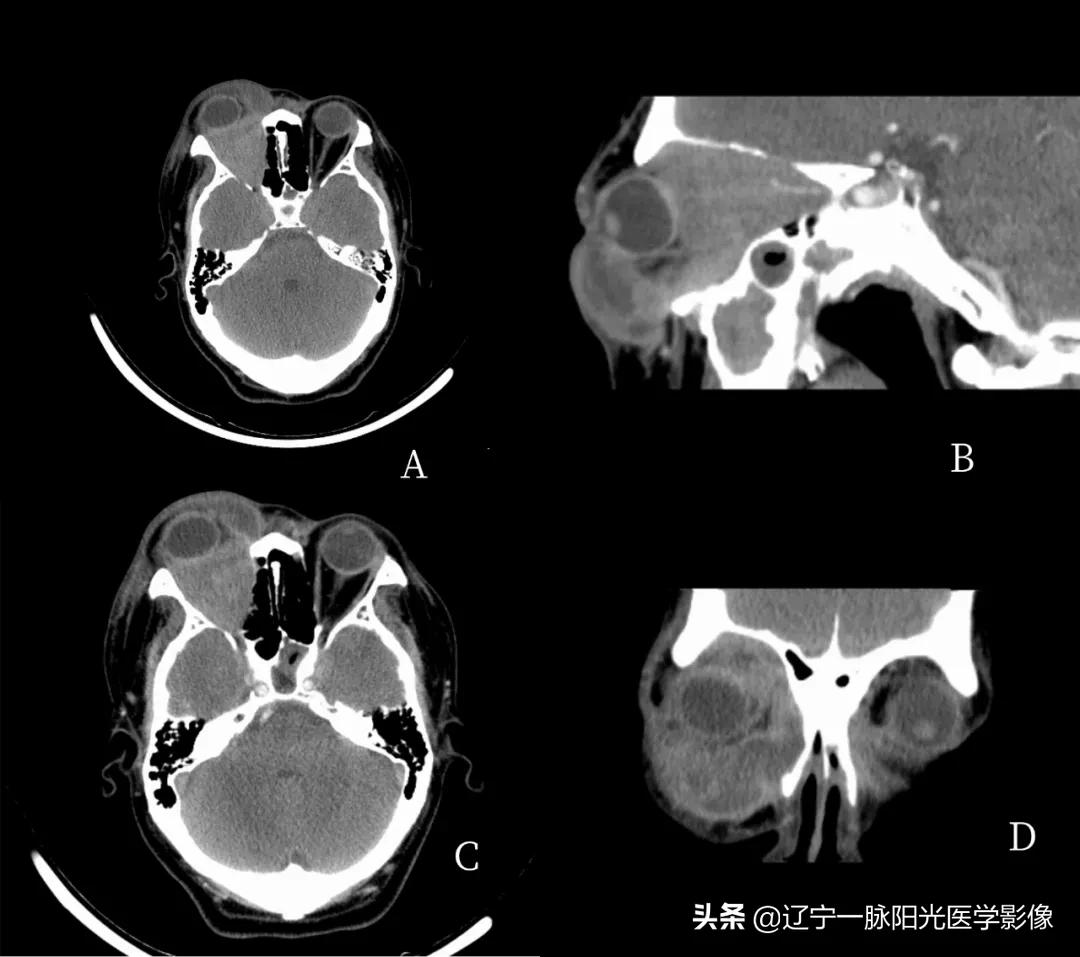

影像所见:

图 A、C 轴位及冠状位示右侧眼睑及球后软组织肿胀,脂肪间隙不清,见混杂稍低软组织密度影,增强扫描轻度强化

图 D 冠状位示右眼球受推外突,病灶包绕右侧视神经及眼肌,视神经及眼肌显示不清,肌肉间隙消失

影像诊断:右眼改变,考虑蜂窝组织炎伴眶内炎性假瘤形成